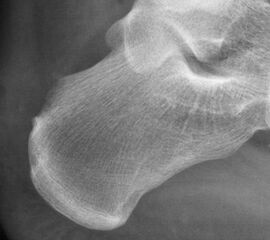

Abbildung 10, Video 5

Das OP-Ergebnis wird mit dem Bildwandler dokumentiert. Hierbei ist es wichtig, auch mediale und laterale Schrägaufnahmen anzufertigen, um keine weit posteromedial oder -lateral gelegenen Exostosenreste zu übersehen (Calcaneus seitlich, sowie 45° Innen- und Außenrotation). Ergänzend zu Röntgenaufnahme sollte der mediale und laterale Calcaneus abgetastet werden, um das Risiko einer belassenen Knochenkante möglichst gering zu halten. Der Hautverschluss erfolgt in Einzelknopftechnik, eine Ruhigstellung ist nicht erforderlich.

Abbildung 11-12

Prä- und postoperatives Röntgenbild.